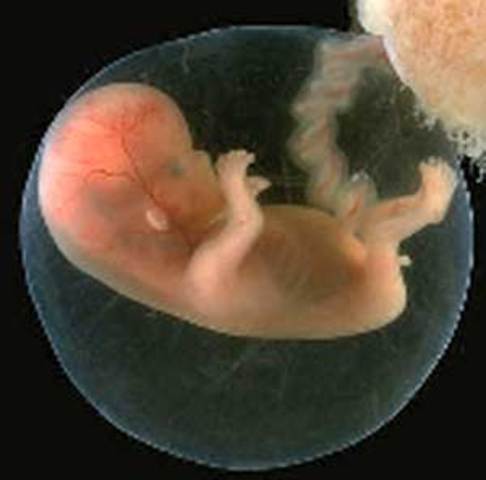

Periodo embrionario

El embrión es considerado a partir de la 4ta semana de gestación y hasta la 8va semana de gestación

Ocho semanas son el marcador del fin del período embrionario.

Durante esta etapa, el embrión humano se ha desarrollado desde una única célula hasta los casi mil millones de células que forman más de 4 mil estructuras anatómicas distintas. A partir de aquí ya recibe el nombre de feto.

El feto ahora posee más del 90% de las estructuras que se encuentran en los adultos.